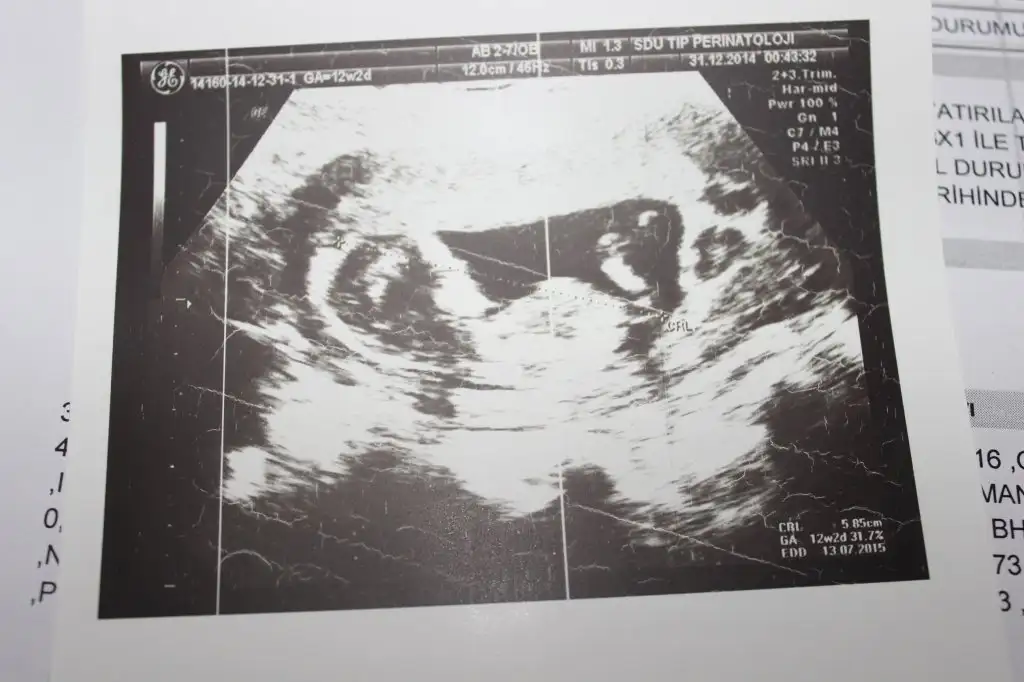

dr soylemeden siz gorun genital nub teorisi ( bebegin cinsiyeti)

IMG_1301.webp IMG_1302.webp IMG_1303.webp IMG_1306.webp

OTE="zeynepelas, post: 38719531, member: 602822"]teşekkürler bu toda kız gibi 12 haftalık fotosu erkek gibi hayırlısı inşallah heycanlanıyor insan :D[/QUOTE]

Kiz dedigim foto on haftalikmis zaten canm o haftada hepsi kiz gibi gorunur bilseydim kucuk derdim son fotodan belli erkek bebegin geliyor bence

arkadaşlar bana kız diyende var erkek diyende benim bebeğim belli etmiyomu yaa bnde anlayaadım ne paralel ne yukarı dogru :D